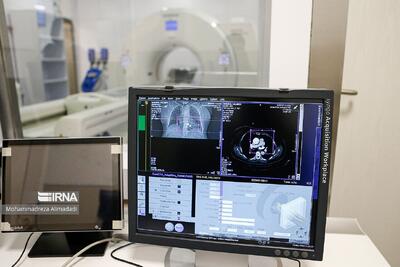

تشخیص سرطان کلیه معمولاً از طریق سونوگرافی، سیتیاسکن،امآرآی و آزمایش خون و ادرار انجام میشود. روشهای درمانی به مرحله بیماری بستگی دارند و شامل جراحی برای برداشتن تومور یا کلیه، ایمونوتراپی، هدفدرمانی و گاهی شیمیدرمانی است.

شرکت مایکروسافت بهعنوان یکی از غولهای فناوری دنیا با کمک هوش مصنوعی، ابزاری برای تصاویر آنالیز دقیق تصاویر پزشکی ارائه کرده است. اهمیت تشخیص درست جزئیات تومور و سلولهای سرطانی در تشخیص این بیماری و یا درمانهای پیشرفته مانند ایمونوتراپی، اهمیت زیادی دارد.